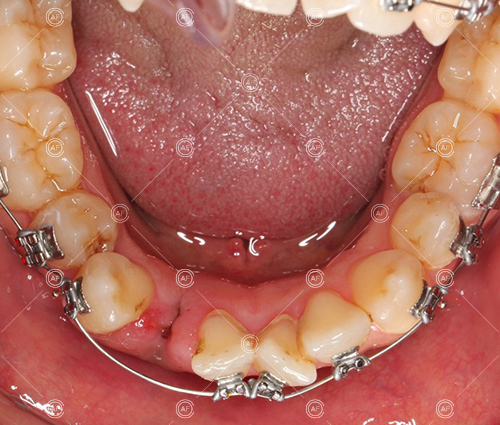

- Extraction of upper right 5, upper left 4, lower left 5, lower right 5

Residual space from the extractions were closed using upper and lower nickel titanium closing coils. Class 2 elastics were used to facilitate space closure in order to gain class 1 buccal segments.

MH debonded in December 2020, with overall treatment time of around 14 months.